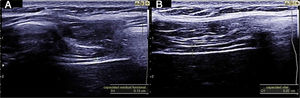

Measuring diaphragmatic thickness is another method currently used to determine diaphragmatic muscle mass and assess the thickening fraction (TF). For this measurement, a high-frequency linear transducer is used, placed between the last intercostal spaces. This locates the zone of apposition, where the diaphragm is in direct contact with the chest wall. The diaphragm is identified as a hypoechoic strip flanked by two hyperechoic lines, which correspond to the pleura and peritoneum. The TF is the ratio between diaphragm thickness at rest (functional residual capacity) and in maximum inspiration (vital capacity) (Figs. 1 and 2).